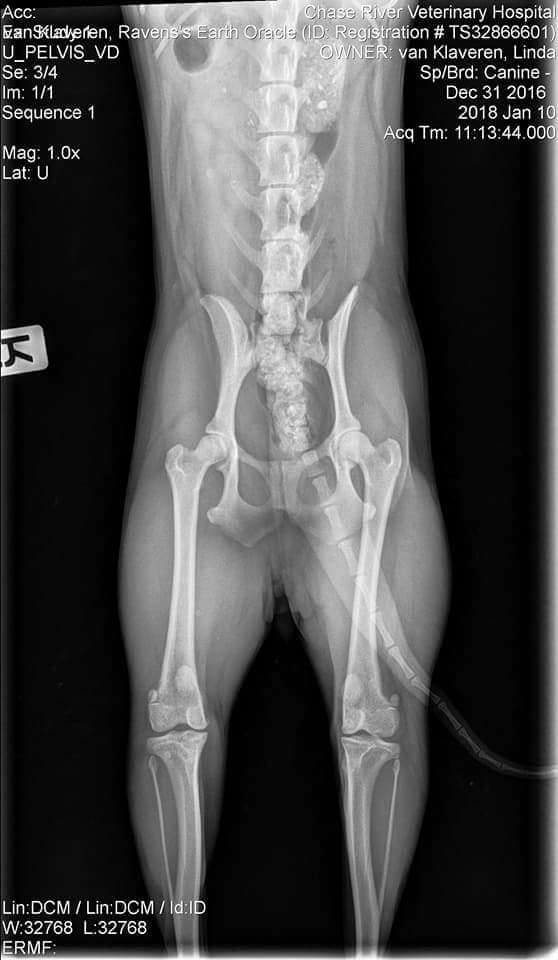

OFA Test Results:

Test Date - Jan. 10, 2018

Report Date - Jan. 15, 2018

· ELBOW PRELIMINARY NORMAL

· HIPS PRELIMINARY GOOD

· CHC-LP23/12F-VPI LEGG-CALVE-PERTHES NORMAL

· CHC-PA676/12F/P-VPI PATELLA NORMAL - PRACTITIONER